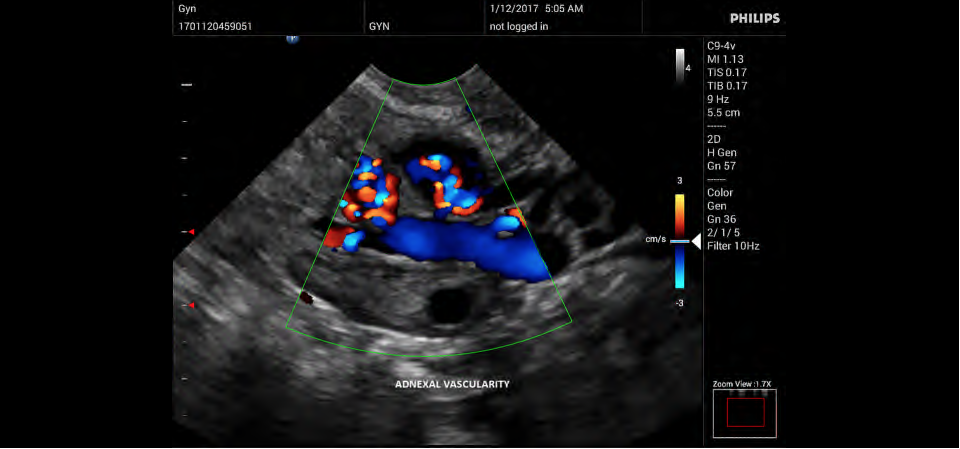

• Акушерство и гинекология;

• Цветное допплеровское картирование

• Направленный энергетический допплеровский режим: Дополнительно к возможностям визуализации сосудов в стандартном энергетическом режиме добавляется информация о направлении. Этот режим полезен для визуализации мелких сосудов в качестве замены цветного допплеровского картирования.

• Конвексный УЗИ датчик Philips C9-4v